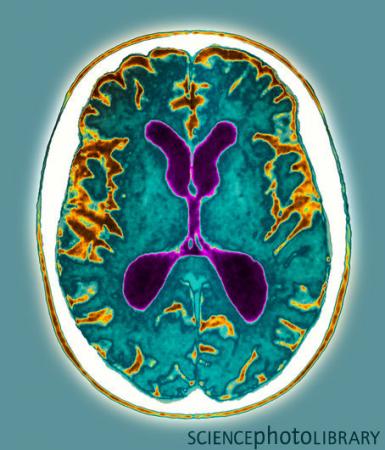

美国宾州大学医学院和国立老年研究所的科学家,应用MRI新技术分析大脑的组织成分和结构,可发现存在轻度认知障碍(MCI)的患者(MCI是早期阿尔茨海默病的症状),从而有助于早期诊断AD。

通过该技术检查早期脑部异常,从而对早期诊断和治疗AD发挥重要作用。该研究第一次显示出应用MRI技术可以鉴别大脑组织类型从而非常准确地诊断患病个体。